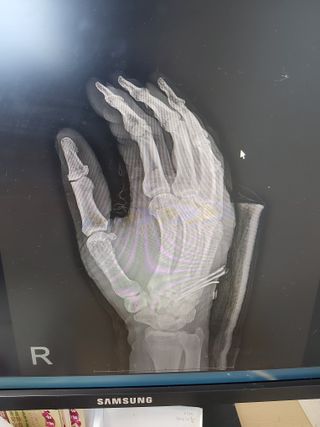

제가 6월1일 농작업하다

다쳐 현제 치료중이오니 많은 기도 부탁 드립니다, 🙏

제가 5월말 모내기를 끝내고 밭작물에 지하수로 물을대다가 고무호스에 걸려서 넘어져 많이 다쳐서 활동 자유롭지 못합니다.